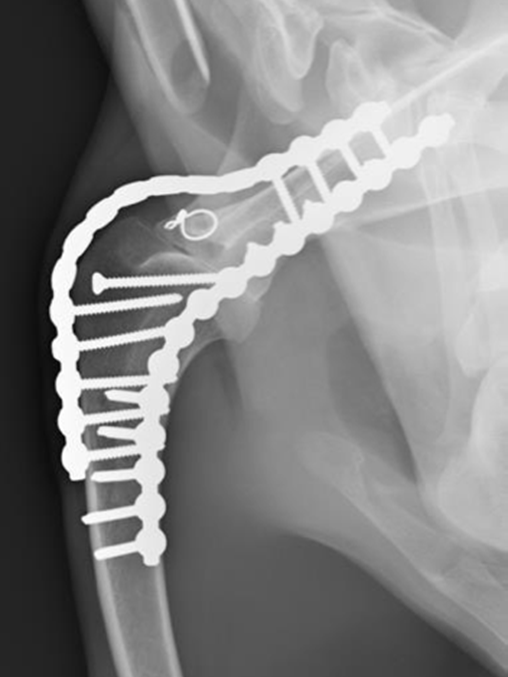

In very severe cases shoulder arthrodesis (Fusion) may have to be the only option available. This is clearly a very big undertaking and is a last resort procedure however the surgery and potential for problems has been improved considerably by using CT data and custom made cutting and reduction guides. We are actively working on developing shoulder replacement but this is not yet to a point in which we can use clinically yet (2018).